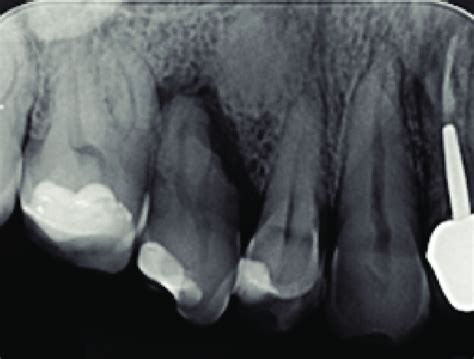

- Radiografías: Las radiografías dentales son una herramienta esencial para detectar quistes bucales que no son visibles a simple vista. Generalmente los quistes dentales se observan a través de una radiografía panorámica o una radiografía 3D que es mucho más precisa y exacta.Estos estudios determinarán el tamaño del quiste, su origen, la posición, el estado del diente y de la encía y cómo afecta a los dientes cercanos a él.

- Quiste Radicular: Este es el tipo de quiste más frecuente que podemos encontrar en la boca y se forma como resultado de una infección en la raíz de un diente que se ha muerto o con caries avanzada. Su nombre ya nos indica en qué lugar se encuentra este tipo de quiste dental. En efecto, justo en la raíz del diente. Ya sea por infección por una caries no tratada o por una lesión en la propia pieza, este quiste suele crecer lentamente y ser asintomático. De hecho, se detectan por su tamaño visible. En este caso, la endodoncia suele ser el tratamiento más adecuado. De este modo, se limpia y sella el conducto radicular o, incluso, se realiza una extracción de la pieza.

- Quiste Periodontal Lateral: Este quiste es el quiste más raro y se forma en el hueso, concretamente entre las raíces de los dientes, y suele detectarse en las radiografías que realizamos periódicamente. Por su parte, este quiste dental se produce en el lateral del diente. Normalmente, es indoloro, pero si se lleva a cabo una pérdida del hueso.